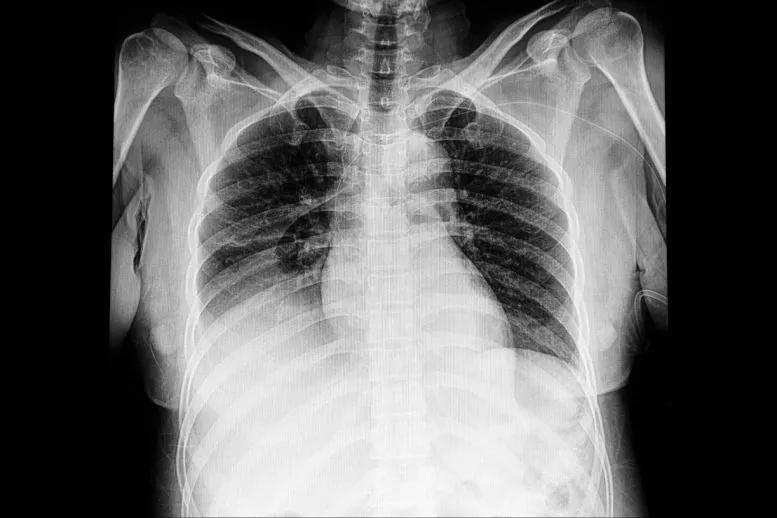

到达医院时,她的心跳很快,胸部X光检查显示肺水肿。进一步的扫描显示,液体已经浸润了心肌,这是一种被称为心肌水肿的紧张迹象。但她没有结构性心脏病。